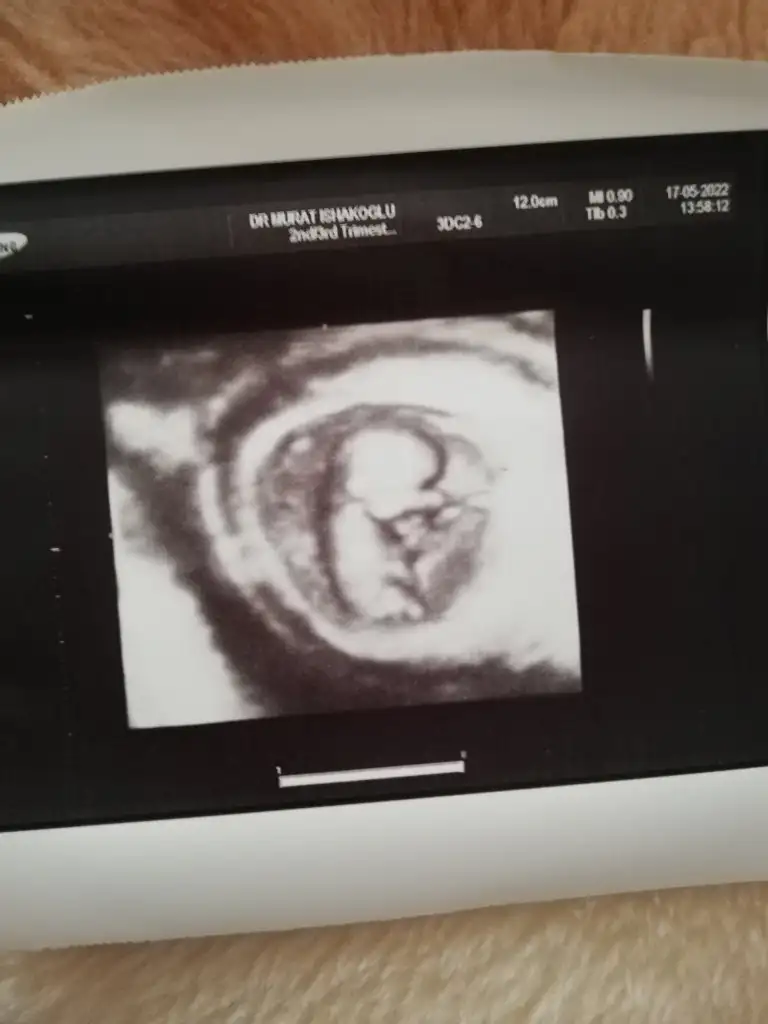

kesen maşallah yuvarlak kız gibi duruyormuş ama paşa benceKiz dedin cnm 16 haftalık oldu ama daha belli degil atiyim yıne ben eski ultrasonu

Canım ben dün yazdım ama cevp yazmamışsın. 11 haftalık karından bakıldı. Bugün gittim 12 haftalık yine söylemedi.kesen maşallah yuvarlak kız gibi duruyormuş ama paşa bence